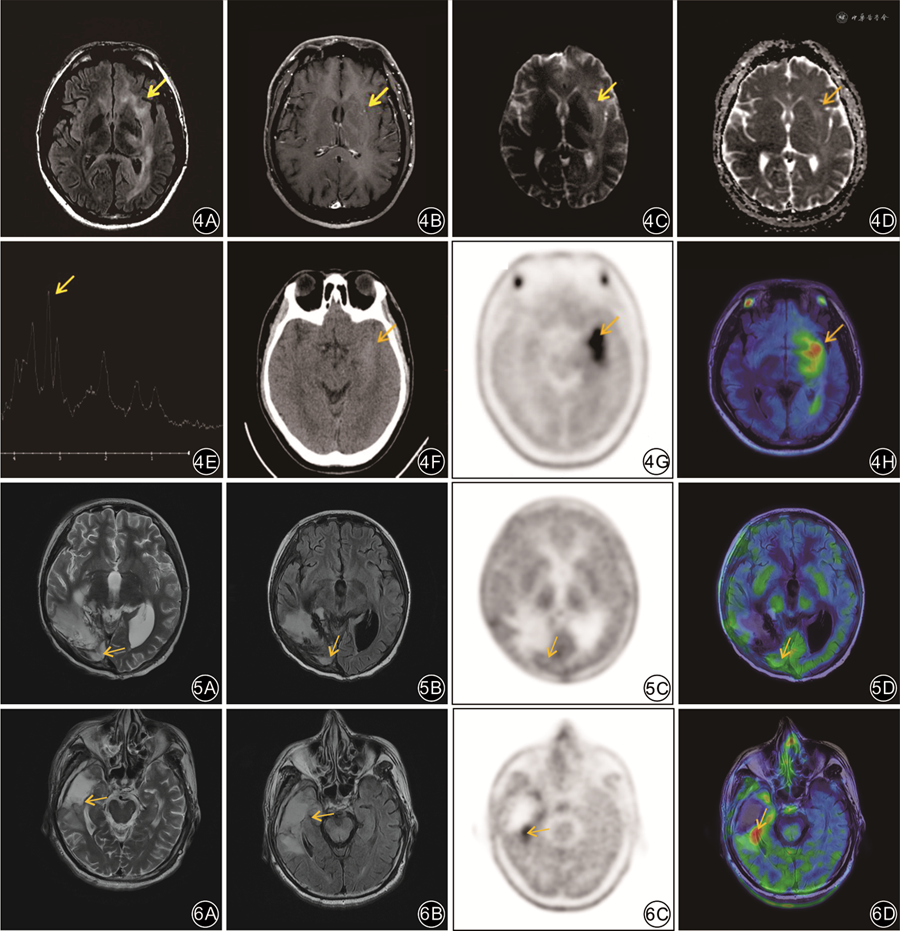

临床实践证实,11C-MET PET/CT在脑胶质瘤的诊断、分级、预后评估、浸润范围的勾画、活检及放疗计划的制定、放射性脑损伤与肿瘤残留/复发的鉴别诊断等方面起到重要作用[8]。同时异机融合软件功能也日益成熟,保证了脑部融合图像的准确可靠,成为提升脑肿瘤诊断的有效策略。本研究结果显示,异机融合11C-MET PET/MRI在原发性和残留/复发性脑胶质瘤的诊断与鉴别诊断方面均有较高的临床应用价值,其诊断效能优于11C-MET PET/CT或MRI单独应用。

本研究结果还显示,11C-MET PET/CT对脑胶质瘤初诊患者的假阳性率较高,说明11C-MET PET/CT在不同病理类型恶性肿瘤的鉴别诊断中存在困难。初诊组41例中,11C-MET PET/CT诊断假阳性6例(14.6%),其中3例转移瘤与3例淋巴瘤被误诊为脑胶质瘤;在融合MRI后,其中5例(5/6)假阳性得到了纠正,因此11C-MET PET/MRI的准确性明显提高,为92.7%(38/41),高于11C-MET PET/CT或MRI,说明MRI可为11C-MET PET/CT诊断胶质瘤初诊带来明显的增益。通过进一步分析PET/MRI的不同影像特征对不同病理类型恶性肿瘤的鉴别诊断价值,发现MRI所提供的瘤周水肿、占位效应与强化特征在不同病理类型恶性肿瘤间差异有统计学意义(P<0.05),可见MRI在不同病理类型恶性肿瘤的鉴别诊断中为11C-MET PET提供重要增益价值。

本研究中,对24例临床怀疑残留/复发性胶质瘤的患者研究结果表明:11C-MET PET在鉴别肿瘤残留/复发与治疗后改变时,其灵敏度与准确度均优于MRI,与以往报道相同[14]。肿瘤细胞处于异常增殖状态,尤其是脑胶质瘤残留/复发时,其恶性程度可进一步增加,氨基酸代谢率也大幅提高,导致11C-MET在病变部位明显富集[15];而由于手术或放疗等治疗手段可能会导致血-脑屏障的损伤、胶质增生与炎性细胞浸润,有时会引起治疗后11C-MET摄取增加,增加的幅度一般会低于肿瘤残留/复发[16],但二者之间的SUVmax值仍会存在一定的重叠。Tripathi等[17]研究表明,肿瘤与正常脑组织的SUVmax比值(T/N)>1.9是11C-MET PET/CT区分残留/复发性脑胶质瘤与治疗后改变的最佳截断值,灵敏度与特异度可达95%与89%;Deuschl等[18]以T/N1.47作为最佳截断值,灵敏度与特异度分别为76%与87%。D'Souza等[19]对11C-MET PET/CT与MRI对脑胶质瘤治疗后是否残留/复发的评估效能进行比较,结果显示11C-MET PET/CT在识别肿瘤复发/残留方面表现出更高的灵敏度(94.7%),MRI则表现出更高的特异度(90.0%)。在本研究中,11C-MET PET/CT对残留/复发性胶质瘤诊断灵敏度(86.7%)高于MRI(66.7%),MRI的特异度(77.8%)高于11C-MET PET/CT(66.7%)。因此,两者融合可在一定程度上优势互补,大大提高诊断性能(95.8%),与既往研究结果相仿(96.0%)[18]。

综上所述,11C-MET PET/CT在区分原发性胶质瘤与良性病变、残留/复发性脑胶质瘤与治疗后改变方面具有明显优势,ASL、MRS也具有重要意义,二者可强强联合;但11C-MET PET/CT在不同病理类型恶性病变的鉴别诊断方面存在不足,而MRI的图像特征(瘤周水肿、占位效应及强化特征)则对其有很大的弥补作用。11C-MET PET/MRI在脑胶质瘤初诊与治疗后评估中具有重要应用价值,其诊断效能较11C-MET PET/CT或MRI单独应用均有明显的提升。